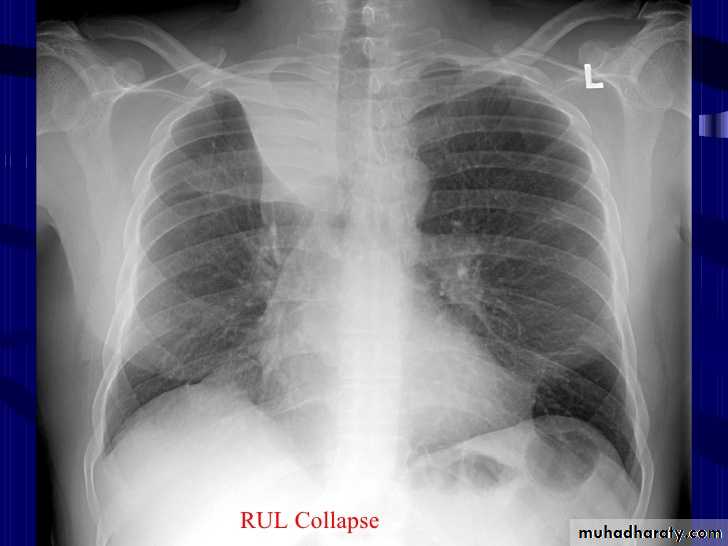

Golden S sign collapse with RT ULC

41.RT UL collapse

42.RT UL collapse

43.golden S sign